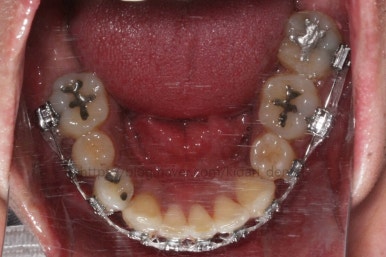

부산치아교정 키다리아저씨치과에 처음 내원 당시의 입안 모습입니다.

여러 가지 문제점이 있는데 하나씩 살펴볼게요.

치열이 많이 삐뚤하네요.

많이 삐뚠 상태에서 장기간 사용하다 보면 안좋은 방향으로 치아가 힘을 받게 되고 마모나 치아 목부분 패임이 심해집니다.

양치가 힘들어요. 양치가 힘들다 보니 세게 닦게 되고 치아 손상은 더 심해져요. 25세의 나이였는데 나이에 비해서 치아나이가 굉장히 많은거죠.

왼쪽 아래 작은 어금니는 아래쪽으로 많이 꺼져있네요.

화살표를 보면 작은 어금니 하나가 아래로 꺼져있는데, 이 녀석 때문에 애를 먹었네요. 훨씬 치료가 빨리 끝날 수 있었는데 이 치아가 워낙 잘 안움직이는 바람에 2년 개월정도로 치료기간이 많이 걸린 편이었어요.

대신 위쪽 아래 작은 어금니가 애를 먹이고 있어요. 낚시줄처럼 부여매고 끌어올리는게 보이실거에요.

뼈에 단단히 붙어 안움직이는 경우를 "유착치아"라고 표현하는데, 유착치아라면 해당 치아를 움직이는 것을 포기했어야 했어요.

그래도 조금씩이라도 움직이고 있어서 계속 시도했습니다.